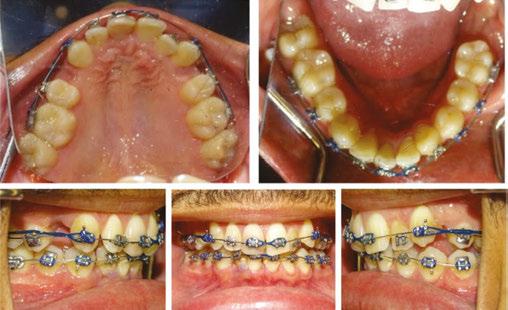

Treatment progression

The patient’s general dentist has monitored the PARLs and will continue to do so, but no further treatment regarding the PARLs was recommended by the general dentist at that time. The patient was made aware of several possible complications to treatment, including that an endodontic procedure may be necessary in the future, the PARL-associated teeth may be ankylosed, or root resorption may occur. The patient was bonded on

January 21, 2021 and had all extractions completed on February 10, 2021. Within 5 days of the extractions taking place, power chains were placed to close extraction spaces and preserve remaining alveolar bone and minimize adaptive bone resorption of the extraction sites. (Figures 7A, 7C, and 7E).

At this stage in treatment, our main goal was to level and align, close extraction spaces to relieve crowding, and monitor any signs of ankylosed teeth. Rotations on the mandibular teeth were corrected in a .016 NiTi wire (Figures 7C and 7E versus Figures 8C and 8E). Efforts were made to minimize roundtripping of incisors via bypassing upper left lateral incisor.

Once appropriate anchorage was burned, and the spaces between the maxillary canines and first molars were closed, a closing looped arch wire was bent using a .018 x .025 stainless steel wire (.018 anterior slot size, Roth Rx) and placed on October 13, 2022. This wire aided in correcting torque, retracting the maxillary anterior teeth, bite opening, and closing remaining spaces between the maxillary canines and lateral incisors (Figures 9C and 9E). At the same time, power chains were used to consolidate remaining spacing in the lower arch (Figures 9B and 9E).

Minor adjustments in torque were then resolved with .016 x .022 NiTi wires placed on June 22, 2022. By October 19, 2022, the patient’s spaces were consolidated, and all teeth were properly leveled and aligned. The finishing stage of treatment (Figure 10) involved minor detailing and Class II elastic wear. The tissue is healthy, spaces are consolidated, the patient is happy with the current esthetic result.

Figure 7: Progress intraoral photos taken on February 10, 2021 Figure 8: Progress intraoral photos taken on April 7, 2021 Figure 9: Progress intraoral photos taken March 3, 2022 Figure 10: Progress extraoral (Figures 9A–9C) and intraoral (Figures 9D–9H) photos taken January 18, 2023 A. A. A. A. D. F. G. H. B. E. C. C. C. C. D. D. D. E. E. E. B. B. B.